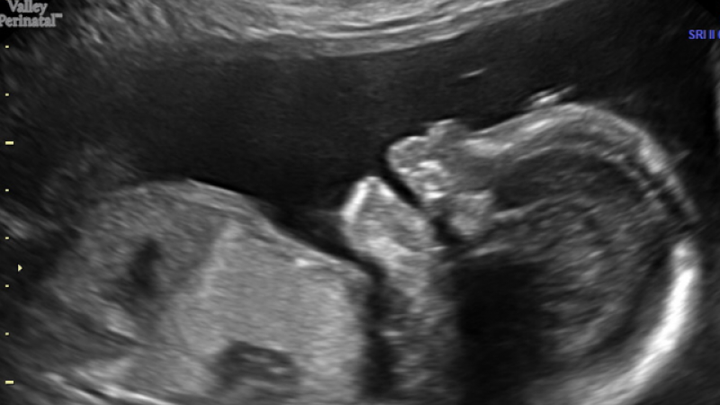

My beautiful younger sister Rachel is pregnant with her second child, a baby girl named Ayden. At approx. 20 weeks, during a routine anatomy scan, Ayden was diagnosed with Type III CPAM. CPAM is a rare lung abnormality that affects 1 in 30,000 babies and produces a pulmonary mass with cysts. Type III occurs in only 10% of these cases, and in only 0.0003% of babies overall. The mass in Ayden's chest is the largest her physicians and surgeons have ever seen and if it doesn't reduce in size, can result in fetal hydrops (fluid in multiple areas of the baby's body) and heart failure. In both of these scenarios, Ayden's chance of survival is extremely low.

To care for herself and Ayden, Rachel and her family have suddenly uprooted from Phoenix to Houston to be near a children's hospital that can care for them both. She currently requires weekly ultrasounds to monitor Ayden's condition and steroid shots to hopefully reduce the size of the mass. If Ayden's condition doesn't improve, she may require surgery in-utero or early delivery via C-section to receive immediate surgical intervention. Any surgery puts the baby's life at risk, as well as my sister's.